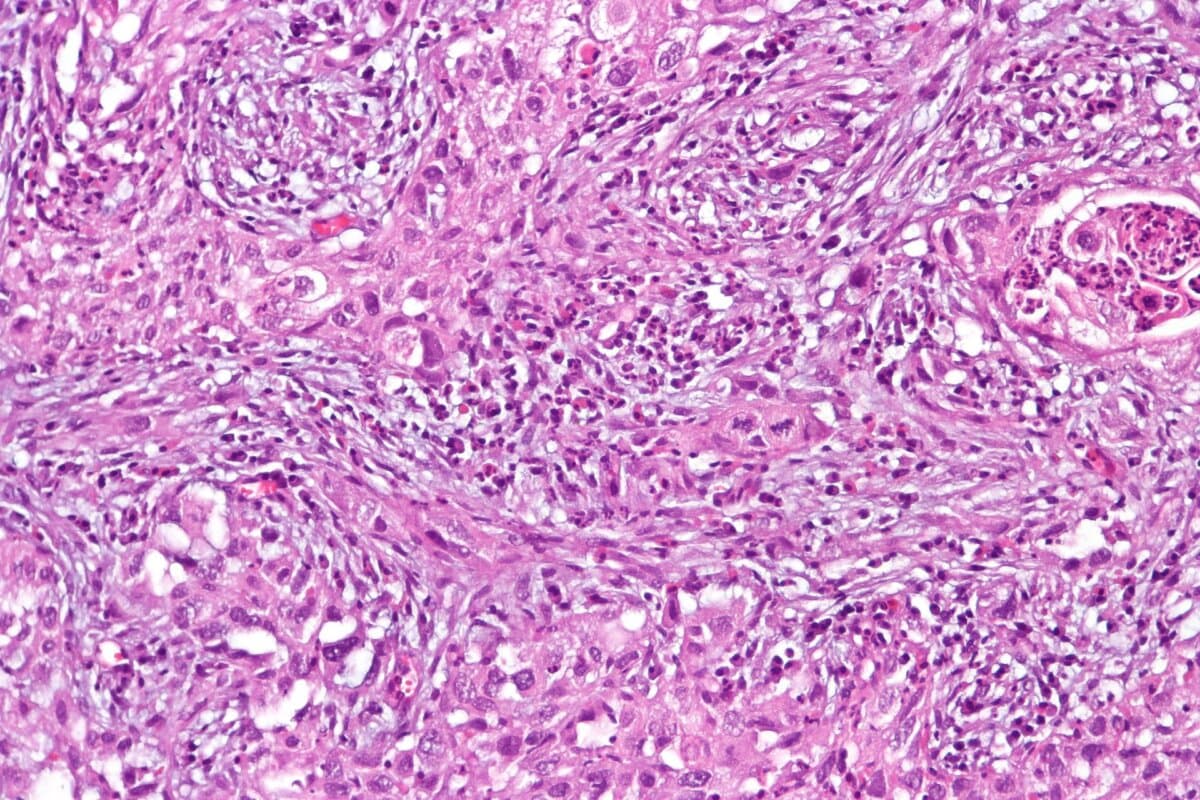

- Histopathologie: Eine als ResNet50 bekannte Architektur sollte lernen, die wichtigsten Eigenschaften kompletter Objektträger mit HE-gefärbten Gewebeschnitten zu identifizieren.

- Histopathologie: Ein vortrainiertes neuronales Netzwerk namens HoverNet ist in der Lage, bestimmte Zelltypen anhand ihrer Kernmorphologie zu unterscheiden. Die Zelltypen wurden kartografisch erfasst, in Regionen unterschiedlicher Wichtigkeit unterteilt und die Häufigkeit jedes Zelltyps ermittelt.

Der dritte Zweig des Modells nutzte das Tumor-Stroma-Verhältnis zur Vorhersage. In Bereichen, denen es eine hohe Bedeutung zumass, korrelierte ein hoher Stromaanteil mit dem Nicht-Erreichen der pCR. «Dies zeigt, dass das Modell autonom etwas über die Tumorbiologie gelernt hat», sagt der Referent